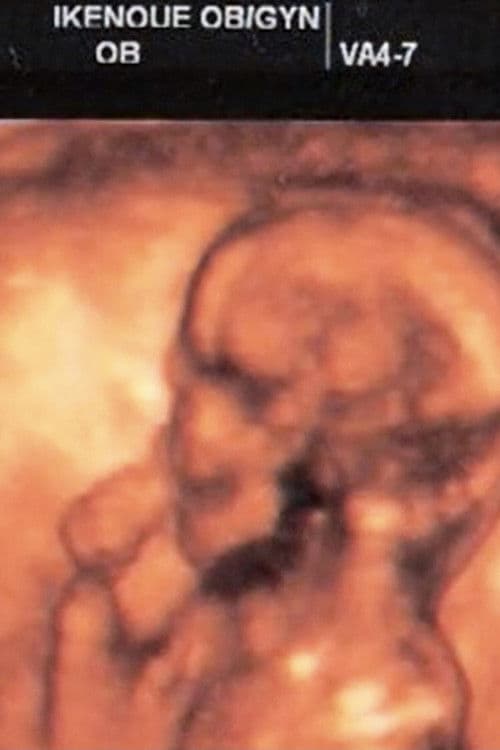

Genre: Runtime: 0h 20mRelease: 1st January, 2008Plot: I went to the company to get up in the morning. And I saw a video taken by a mobile phone. It's a festival to raise the large kite that Hamamatsu festival of Shizuoka. They raise the kite when the first child is born. I was printing the video to OHP. And I cut it to 35mm film. I then projected it. My wife and I went to raise the kite to the park. I attached a camera to thekite. The ground looked like my wife's belly. My wife gave birth to a child. We named her "Nemu". She was born in 2005. Nemu became one year old. She became able to walk. I wanted to celebrate with everyone.